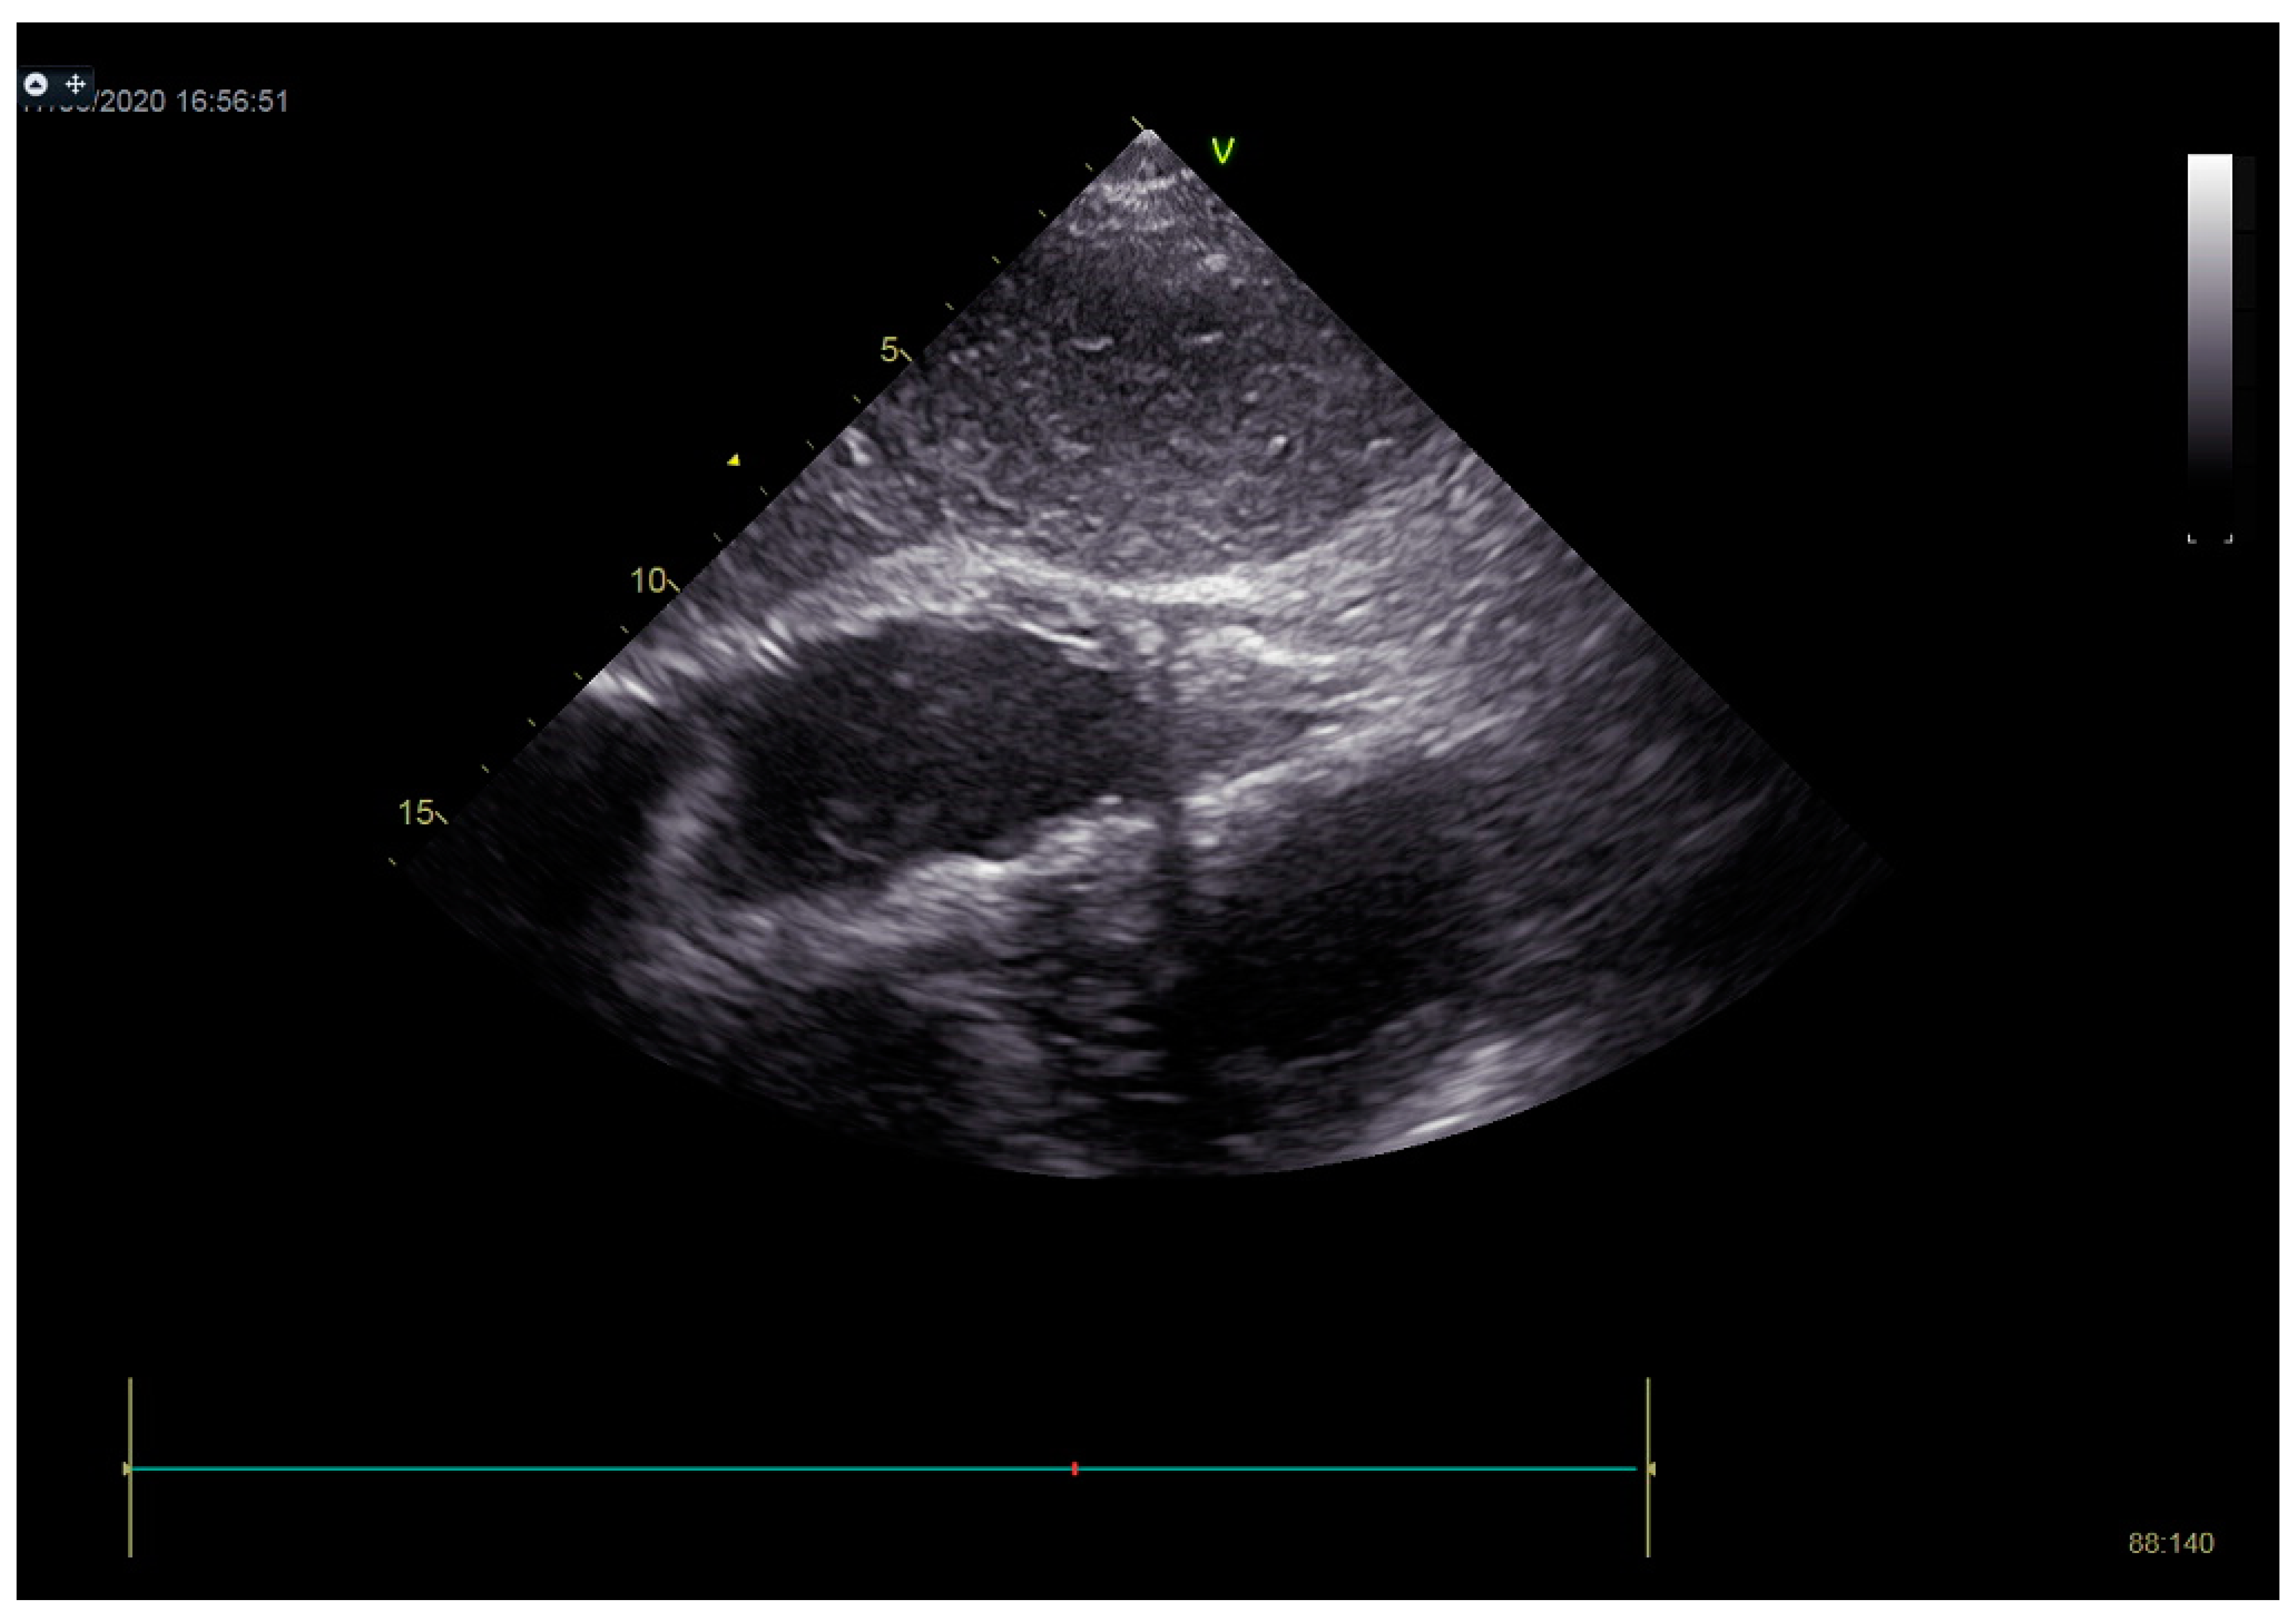

In the following course of treatment, the patient became hemodynamically unstable, despite high doses of inotropes and vasopressors. Echocardiography registered a more significant amount of effusion around the heart compared to the previous exam, with signs of cardiac tamponade (Figure 9). Pericardiocentesis was performed, and 260 mL of hemorrhagic fluid was drained (Figure 10).

Figure 9.

Echocardiography registered a larger amount of effusion around the heart compared to the first exam, with signs of cardiac tamponade.